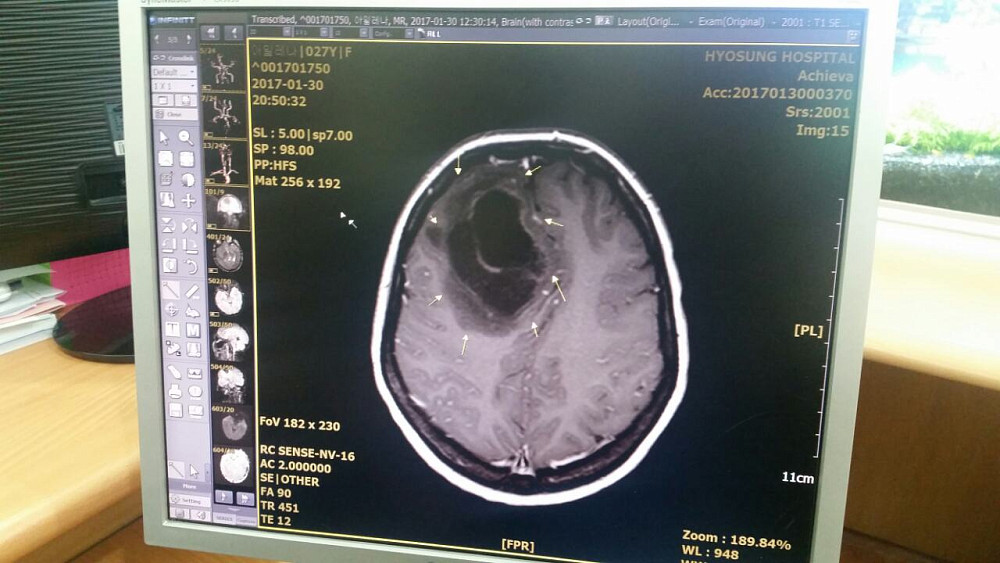

Алене Зуевой предстоит операция на головном мозге

Почти четырехдневное нахождение в корейском стационаре обошлось родственникам в 158 тысяч рублей. Все расходы покрыли неравнодушные жители Бурятии, которые откликнулись на призыв о помощи. Но радоваться пока рано. У девушки выявили рак головного мозга, ее необходимо срочно транспортировать в Россию.

- Корейские врачи говорят, что лучше всего провести операцию в России, потому что после оперативного вмешательства предстоит долгая реабилитация. Это очень дорого обойдется, если делать в Корее, - рассказывают друзья.